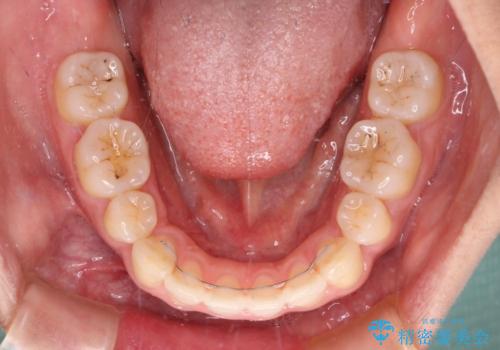

4本の歯を抜歯したことで、飛び出していた口元が引っ込み、横顔が大きく改善されました。

咬み合わせが悪化することのないようにスペースを閉じていくことができ、比較的スムーズに治療を進めることができました。